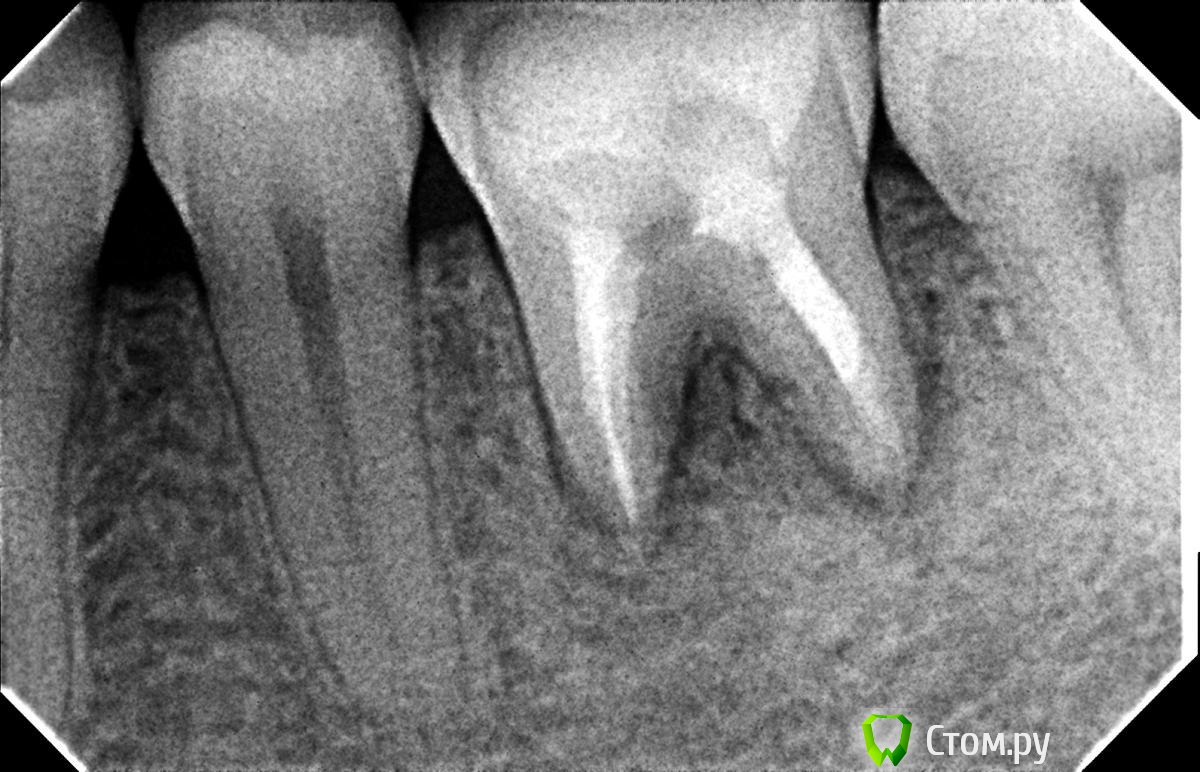

Hans85 Опубликовано 8 января, 2014 Поделиться Опубликовано 8 января, 2014 Только зарегистрировался на форуме,хотелось бы познакомится с коллегами.для начала выкладываю небольшой кейс с названием "Почти мини".Направлен пациент прошло 6 месяцев после фиксации композитной вкладки,заболел.Эндо без рук (только контроль проходимости 10 К-file)Rece+ProFile,пломбирование волна.Всем здравствуйте.P.S Сан Саныч привет)). 12 Ссылка на комментарий

Мартовский Опубликовано 8 января, 2014 Поделиться Опубликовано 8 января, 2014 Только зарегистрировался на форуме,хотелось бы познакомится с коллегами.для начала выкладываю небольшой кейс с названием "Почти мини". Направлен пациент прошло 6 месяцев после фиксации композитной вкладки,заболел. Эндо без рук (только контроль проходимости 10 К-file)Rece+ProFile,пломбирование волна. Всем здравствуйте. P.S Сан Саныч привет)).Отличный доступ и эндо, но желательно выставлять снимок до, с инструментами, и после. Как сказали выше, выстраивать логическую цепочку. Ссылка на комментарий

Л Ю С Я Опубликовано 9 января, 2014 Поделиться Опубликовано 9 января, 2014 Полагаю на КТ будет не такая уж радужная картинка...Чем завершено лечение? Коронка?что коронку не поставил- плохо, но все признаки хилинга имеются Ссылка на комментарий